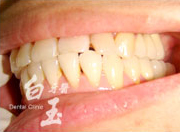

治療前